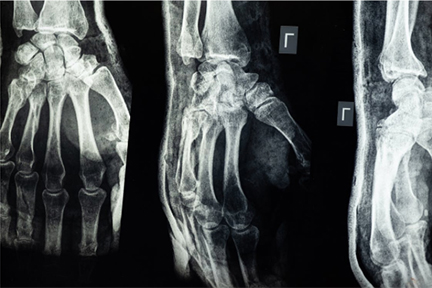

The machine emits a beam of radiation into our bodies. Our dense and hard bones block this beam, so they are visible on the screen below.

The radiation passes into soft tissues such as fat and muscle, which appear grayish in the x-ray scans. The air that is inside our bodies appears in black.